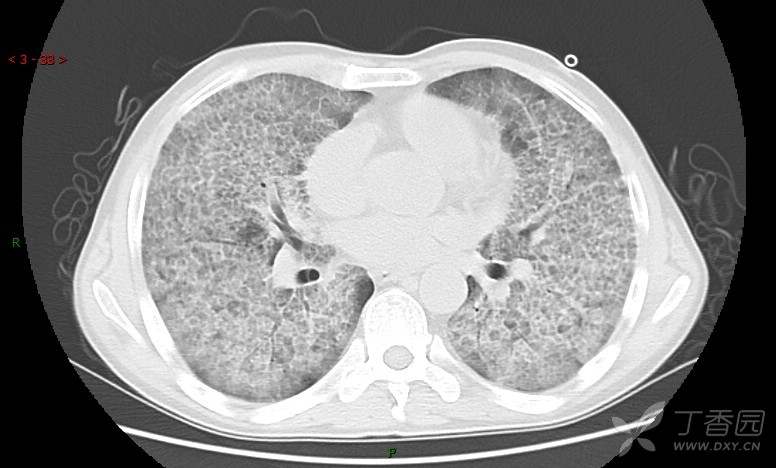

地图+铺路石征=PAP?那升高的CEA怎么说(病例3连发,附其他2例链接)

患者男,42岁,咳嗽半年余,加重伴憋喘2月余。

患者半年余前无明显诱因出现间断咳嗽,干咳为主,偶咳少量黄白痰,剧烈咳嗽或运动后可出现轻度憋喘,无高热、脓臭痰,无胸痛、咯血及晕厥,无低热乏力及盗汗,无心前区压榨感及夜间阵发性呼吸困难,初未在意,未予正规诊治。2月余前患者自觉上述症状较前加重,咳嗽、憋喘明显,黄白色粘痰略有增多,伴有发热,热前伴有畏寒、寒战,体温最高达38.9℃,先后就诊多家医院,入住重症监护室,未行气管插管,考虑“重症肺炎”,给予“美罗培南、复方磺胺甲噁唑”等药物抗感染,“卡泊芬净”抗真菌,并给予“甲泼尼龙”等药物治疗35天,经治疗后症状好转于2018-04-02出院。患者自出院后仅应用中药治疗(具体不详),并给予家庭氧疗,平素仍有间断咳嗽,咳少量黄白色粘痰,活动后憋喘明显,活动耐量差,以卧床为主。

肺内弥漫性网状结节影,PET-CT却无阳性病灶,这是?(附其他2例链接)